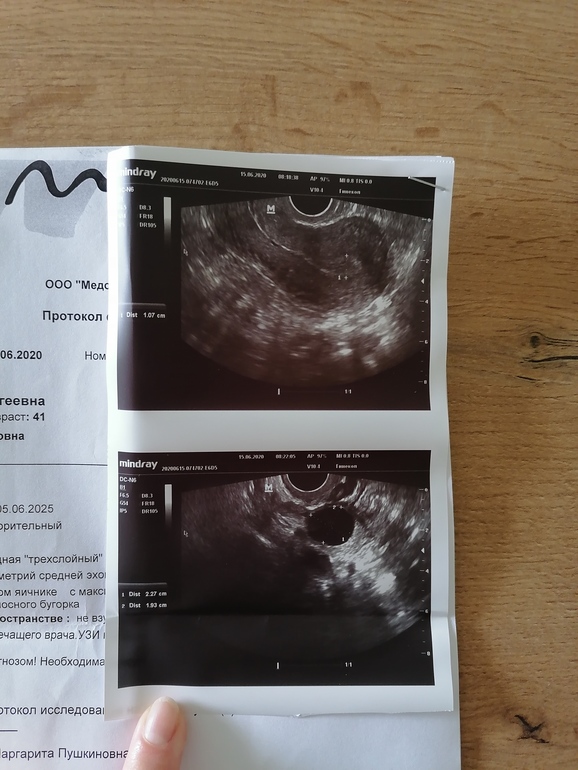

ФолликулометрияДоброе утро. Сходила на узи, там все тфу тфу отлично. Эндометрий шикарный, ананас таки помог😂😂😂. Остался один ДФ в левом яичнике и он уже 21мм и с яйценосным бугорком🙏🙏🙏. В правом яичнике 12мм так и остался, а в левом второй 13мм. Но думаю они расти не будут уже. Девченки, зачихайте меня плиз🙏🙏🙏. Живот уже тянет и утром был секас, а до этого 2 дня перерыв. Завтра закрепим. Думаю овуляция будет сегодня или завтра? Как вы думаете, если есть яйценосным бугорок уже, то должна быть сегодня? Или завтра все же? Но яичник начинает подтягивать.